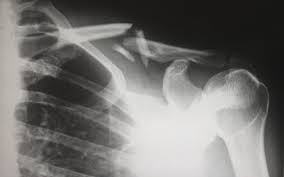

피로 골절이 자주 생기는 부위

피로 골절은 반복적으로 체중이 실리는 부위에서 흔히 발생합니다. 특히 아래 부위는 비교적 자주 언급됩니다.

• 발등과 발바닥 앞쪽

• 정강이 뼈 주변

• 발목과 뒤꿈치 근처

• 장시간 서 있거나 걷는 경우 무릎 아래 부위

러닝이나 등산을 갑자기 시작했거나, 평소보다 활동량이 급격히 늘어난 경우, 또는 딱딱한 바닥에서 오래 서 있는 생활이 이어졌다면 위험이 커질 수 있습니다.